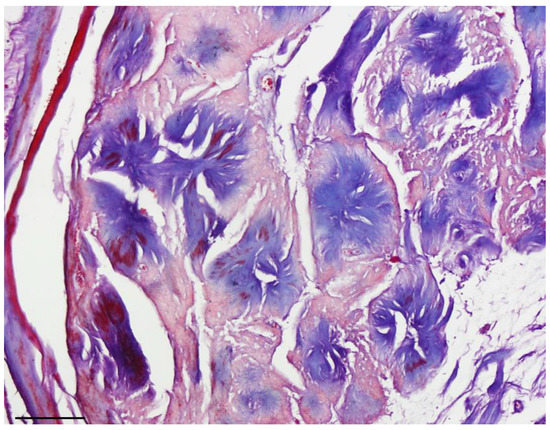

Figure 2. Masson Trichrome, collagen core of rosettes stained blue (40× objective lens, scale bar = 50 μm).

Masson’s trichrome staining confirmed that the central core of the rosettes was composed of collagen fibers. Subsequent immunohistochemical study revealed diffuse expression of S100 protein (as the most commonly used marker to detect tumoral cells) [6] in the tumoral cells, confirming the Schwann cell origin of the tumor (Figure 1 and Figure 2). Additionally, staining for the neural markers showed focal positive expression for Neuron Specific Enolase (NSE) and negative for synaptophysin which confirmed our diagnosis (Figure 3 and Figure 4).

Difference in the size of rosettes is considered an important histological criterion to distinguish neuroblastoma from neuroblastoma-like schwannoma [2,5]. In agreement with previously reported observations, rosettes in our neuroblastoma-like schwannoma case were trichrome positive [12].